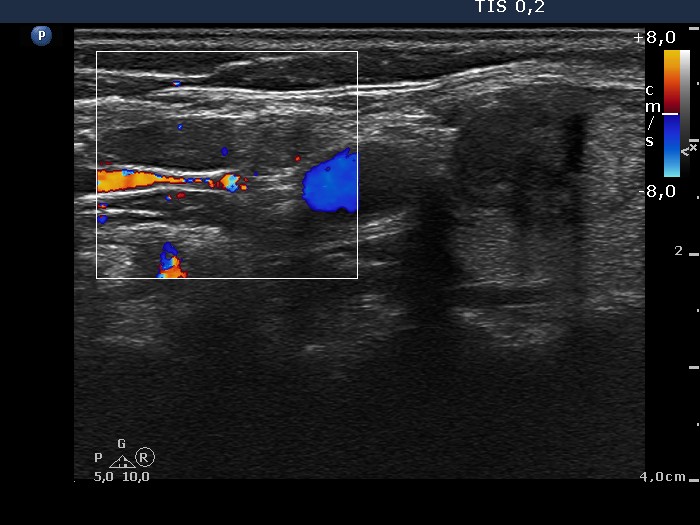

Follicular adenoma - Case 12. (ultrasonographic picture 6)

Above and lateral to the right thyroid , longitudinal scan, color Doppler mode. Doppler mode discloses that the two hypoechogenic lesions above (in the image left to) the artery are not vessels.